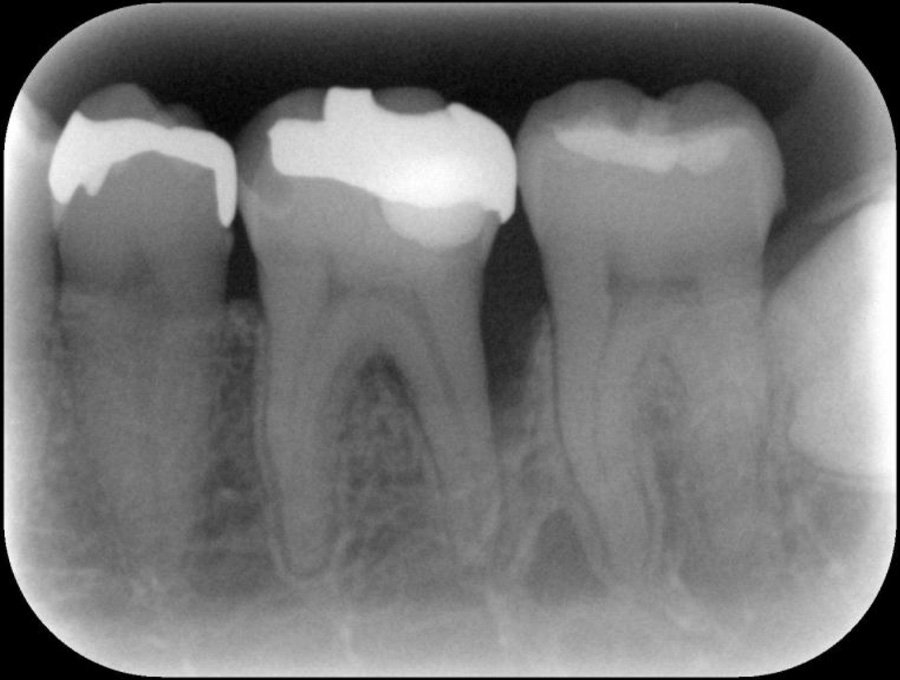

正確な診断

歯周ポケット測定やレントゲン・CT解析など、多角的な検査で歯周病の進行度と原因を正確に把握します。患者さま一人ひとりに最適な治療計画を立て、根拠ある治療につなげます。

精密検査

実際にお口の中の状態をチェックしていきます。レントゲン撮影にて歯や骨の検査を行い、虫歯や治療痕のチェック、歯周病検査などの各種検査を行い、総合的な診断を下します。